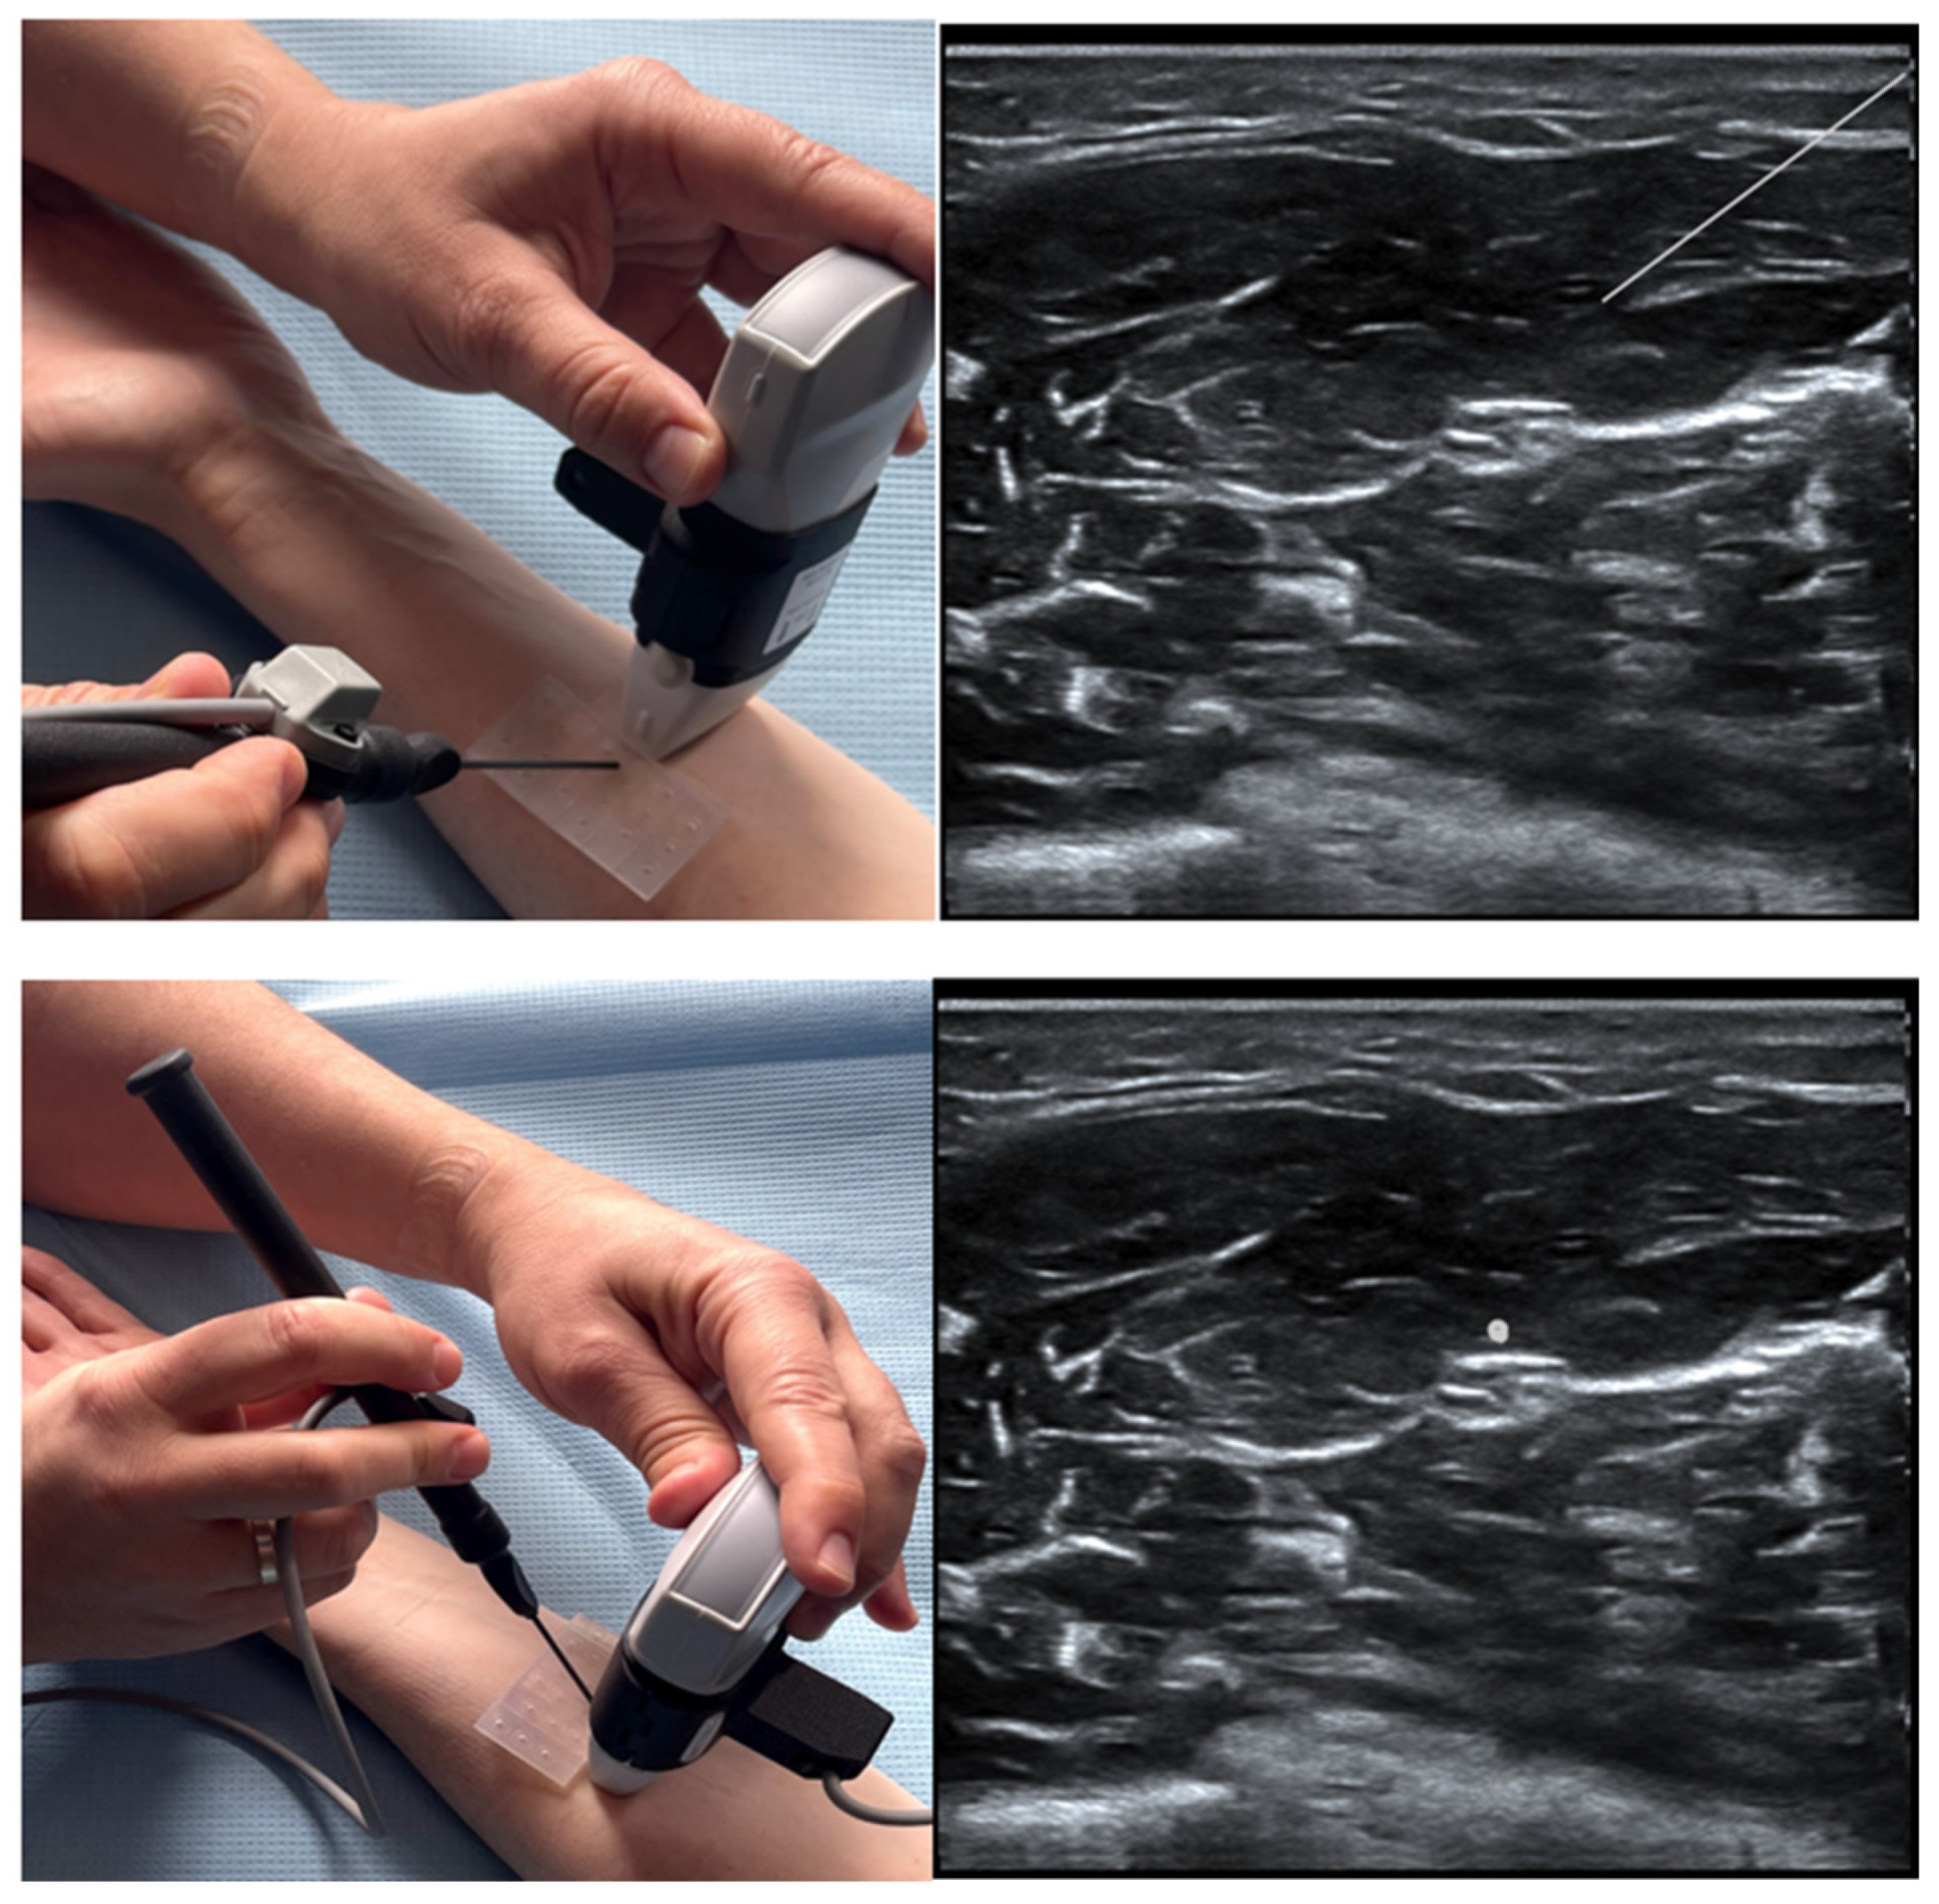

- Shevlin, S.P.; Turbitt, L.; Burckett-St Laurent, D.; Macfarlane, A.J.; West, S.; Bowness, J.S. Augmented Reality in Ultrasound-Guided Regional Anaesthesia: An Exploratory Study on Models With Potential Implications for Training. Cureus 2023, 15, e42346. [Google Scholar] [CrossRef]